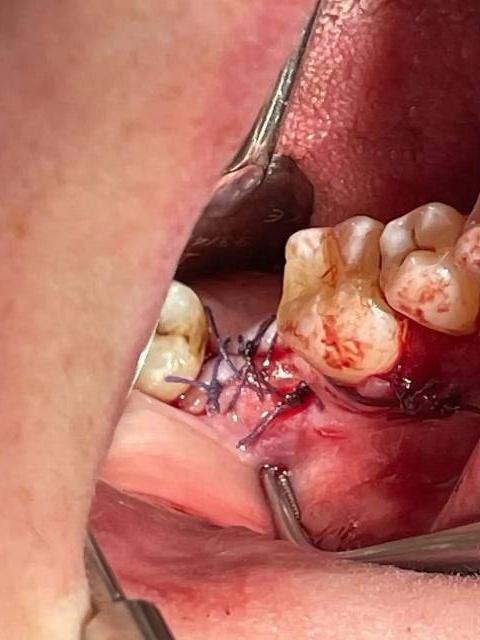

Протокол имплантации

На первом фото «До» — пустота. Отсутствует первый нижний моляр, шестой зуб, который несёт основную жевательную нагрузку. Пациент уже привык жевать на одну сторону, соседи начали потихоньку смещаться, антагонист сверху потерял опору и медленно полз вниз. Классическая картина: один зуб ушёл — и вся система поехала.

Дальше был план, диагностика, расчёты. И момент, который вы видите на втором снимке, — рентген с установленным имплантом. Это не просто "винтик вкрутили". Это хирургическая точность до миллиметра. Здесь важно всё: и ширина кости, и высота, и расположение относительно нижнелуночкового нерва, и угол наклона, чтобы будущая коронка встала идеально в прикус.

Самый интимный кадр — третье фото. Ушитая рана сразу после операции. Для кого-то это просто "шовчик", для меня — момент, когда самое страшное позади. Имплант стоит, кость его приняла, ткани аккуратно уложены на место, швы легли ровно, без натяжения. Теперь главное — покой и время. Природа должна сделать своё дело: кость должна срастись с титаном в единое целое, и через несколько месяцев на этом месте появится опора для новой коронки.